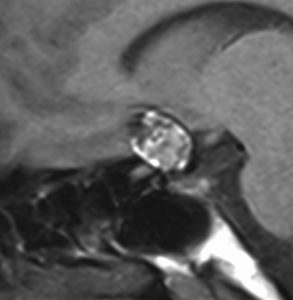

この画像は拡散強調画像 DWI と言います。左が術前,右が術後です。拡散強調画像 DWIで強い高信号になるのが特徴です。しかし,類表皮のう胞でも高信号になるので注意を要します。